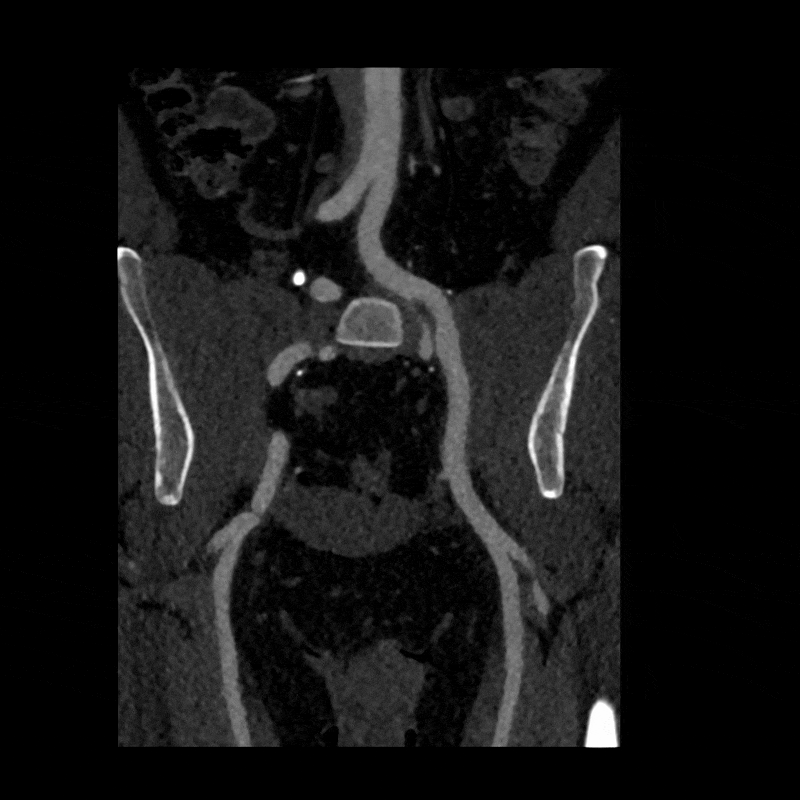

To better visualize the iliac anatomy, CPR loops were created to trace the artery along its course in both relaxed and stressed positions, allowing direct comparison of lumen size and curvature. VR views were generated with and without pelvic and femoral bone to show surrounding anatomical relationships. These complementary views help clarify how limb motion influences vessel shape and highlight narrowing that may be subtle or difficult to appreciate on axial slices alone. (Learn more about CPRs here, and VRs here).

Figure H: Rotational volume render of the iliac arteries in the stressed position.

Figure I: Targeted volume renders of both the relaxed and stressed positions.

When the patient moved into the stressed position, the right external iliac artery showed two areas of luminal narrowing (a temporary decrease in the size of the vessel’s opening). One narrowing was more proximal (closer to the vessel’s origin near the pelvis) at about ten to twenty percent, and the second was more distal (farther along the vessel toward the leg) at about thirty to forty percent. Both returned to a widely patent appearance (fully open) when the leg moved back to a relaxed position.

The left external iliac artery remained patent across positions, and the common iliac arteries were tortuous (naturally curving) without any fixed stenosis. This pattern aligns with external iliac endofibrosis, where motion causes the artery to change shape rather than a fixed obstruction, highlighting why positional imaging can reveal abnormalities that may not appear on routine resting studies.

Figure J (Right): Two areas of narrowing were identified in the right external iliac.